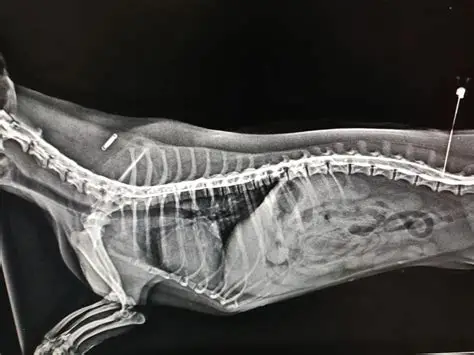

En el Instituto Neurológico Veterinario (INEV) realizamos mielografías, un estudio radiográfico especializado que permite visualizar la médula espinal y sus estructuras mediante la aplicación de un medio de contraste en el espacio subaracnoideo. Este examen se utiliza principalmente para diagnosticar hernias discales, lesiones medulares, tumores o malformaciones que pueden afectar el sistema nervioso central. Gracias a nuestro pabellón de última tecnología y equipo médico especializado en neurología y diagnóstico por imagen, en el Instituto Neurológico Veterinario garantizamos procedimientos seguros, interpretaciones precisas y resultados que orientan al mejor tratamiento para cada paciente.